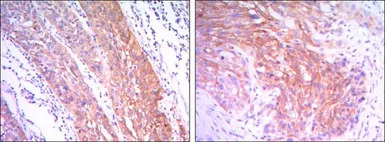

IHC-P analysis of esophagus cancer tissue (left) and human lung cancer (right) using GTX82791 Hexokinase II antibody [3D3].